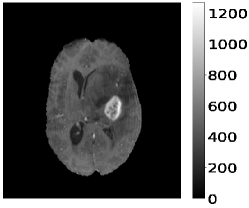

The dataset’s MR images are preprocessed so that the skulls and neck regions are removed. The images are aligned and co-registered to correct any head tilt or mismatches between MR modalities. Each voxel in the image corresponds to of brain tissue. Figure 5 illustrates a 2D axial input MR Images sample and the corresponding ground truth. The input images (a-c) show the different MR modalities: FLAIR, T1CE, and T2 images. The ground truth consists of peritumoral edema (ED) marked in light grey given by an intensity value of , enhancing tumor (ET) represented as a white region with as an intensity value, and the non-enhancing tumor (NET) and necrotic core region (NCR) as dark grey with an intensity value of . The models are evaluated as enhancing tumor (ET), tumor core (TC), and whole tumor (WT). The tumor core corresponds to NET/NCR and the enhancing tumor region. The whole tumor corresponds to all three tumor regions put together. The research aims to learn the ED, NET/NCR, and ET regions.